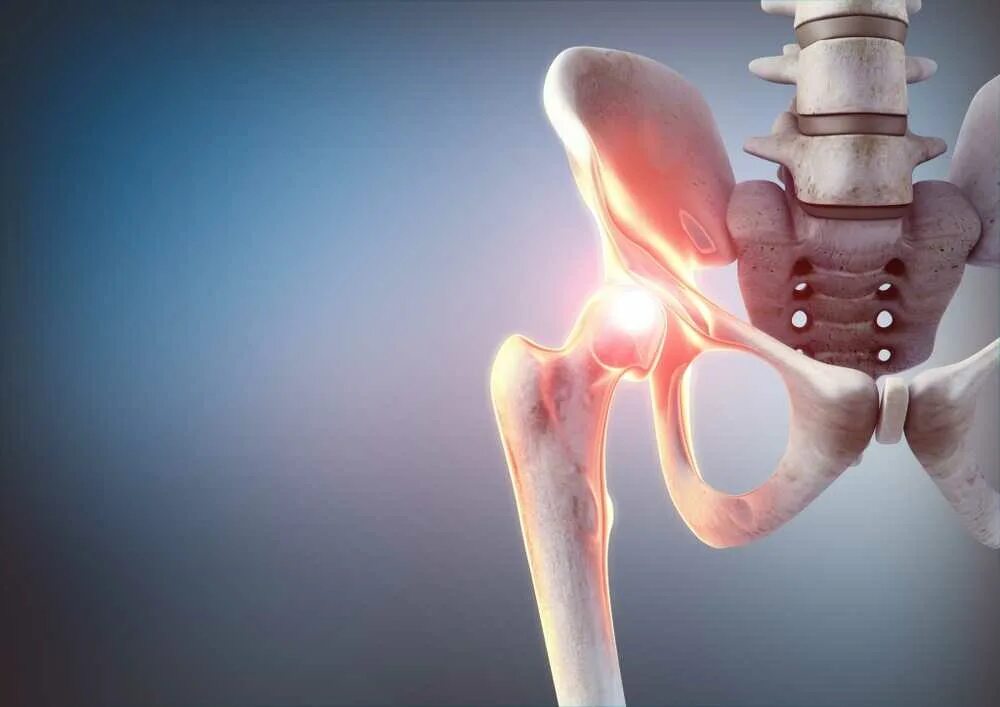

Некроз суставов лечение